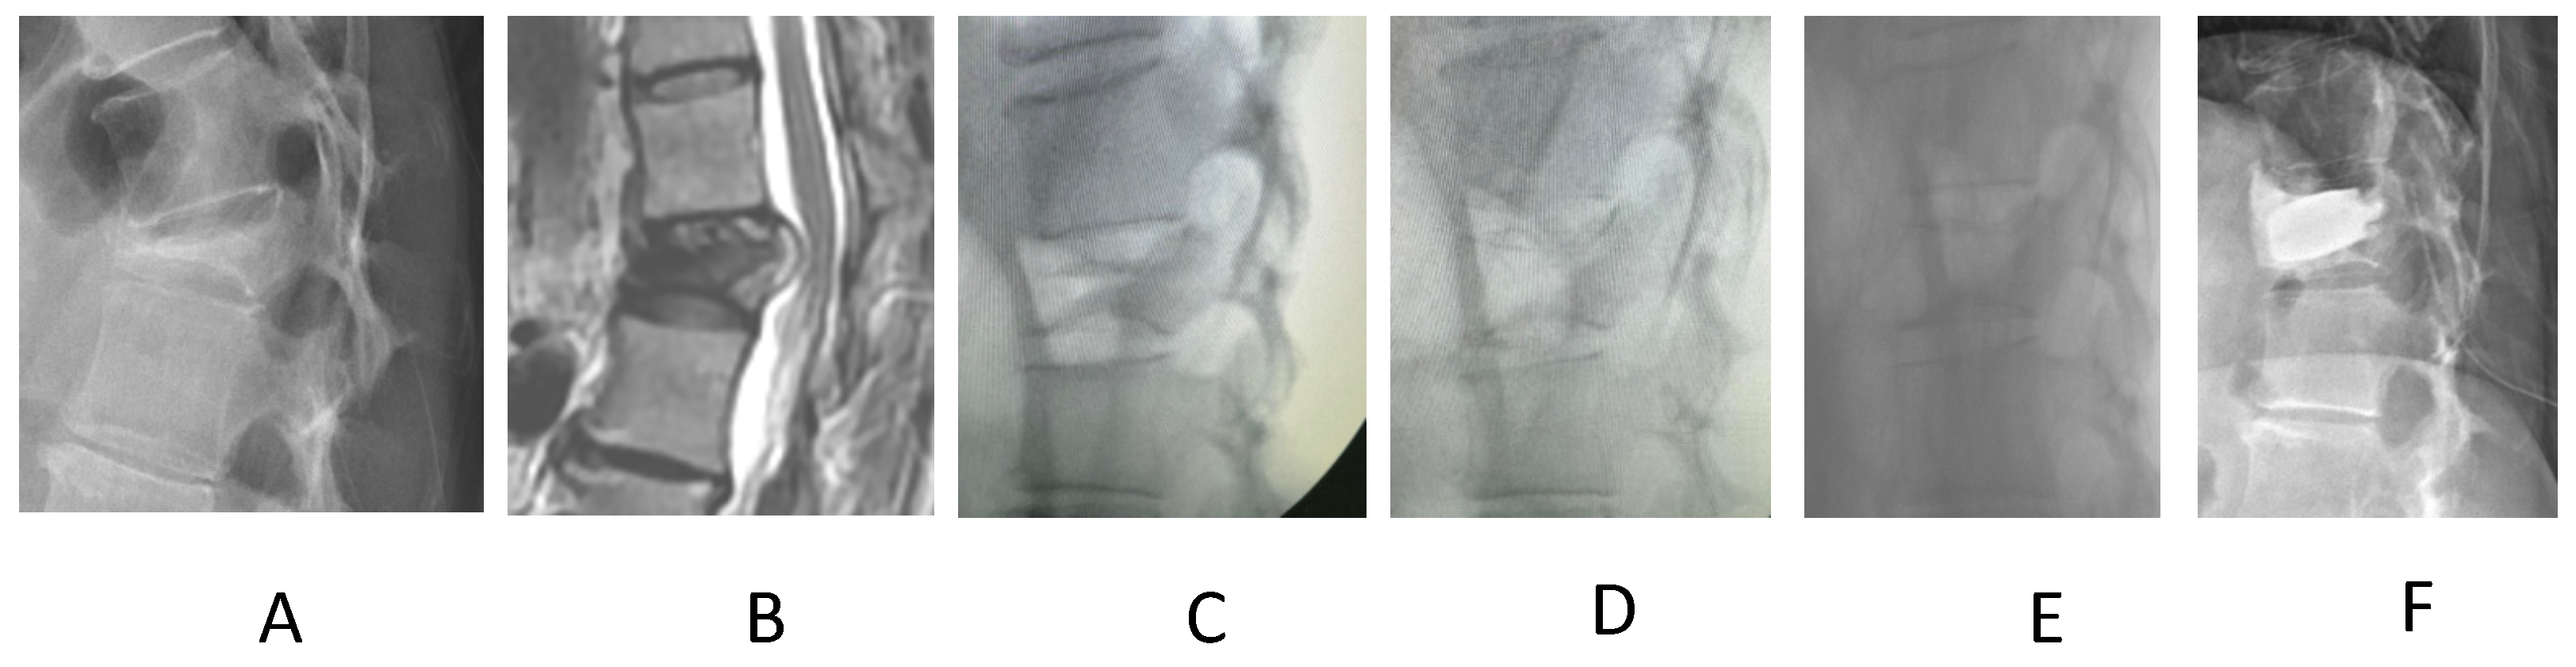

2. Materials and Methods

3. Results

4. Discussion